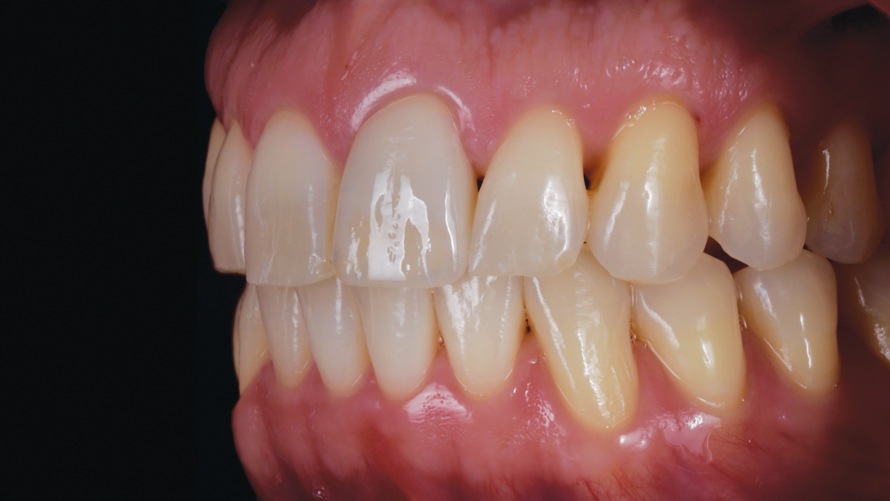

(17.) Case 2: Right- and left-side retracted profile views of the definitive all-ceramic restoration on the maxillary left central incisor.

Figure 17

(1818.) Case 2: Right- and left-side retracted profile views of the definitive all-ceramic restoration on the maxillary left central incisor.

Figure 18

Eight weeks after the initial start of the walking bleach procedure, the final layered lithium disilicate crown was tried-in and evaluated for function and esthetics. Upon patient approval, the intaglio surface of the crown was etched for 20 seconds with a 9.6% hydrofluoric acid etchant, rinsed, and then scrubbed with a 37.5% orthophosphoric acid solution to clean out any ceramic debris. The crown was then placed into an ultrasonic bath of 91% isopropyl alcohol for 5 minutes, after which the intaglio surface was coated with silane and placed under a warm air dryer for 1 minute. A translucent self-adhesive resin cement was used to bond the final restoration to the preparation. The patients both stated that they approved of the form, function, and esthetics of the definitive restoration and that they were very pleased with the final results (Figure 13 through Figure 18). Routine periodic evaluations and radiographs were scheduled to monitor their oral health and esthetics.